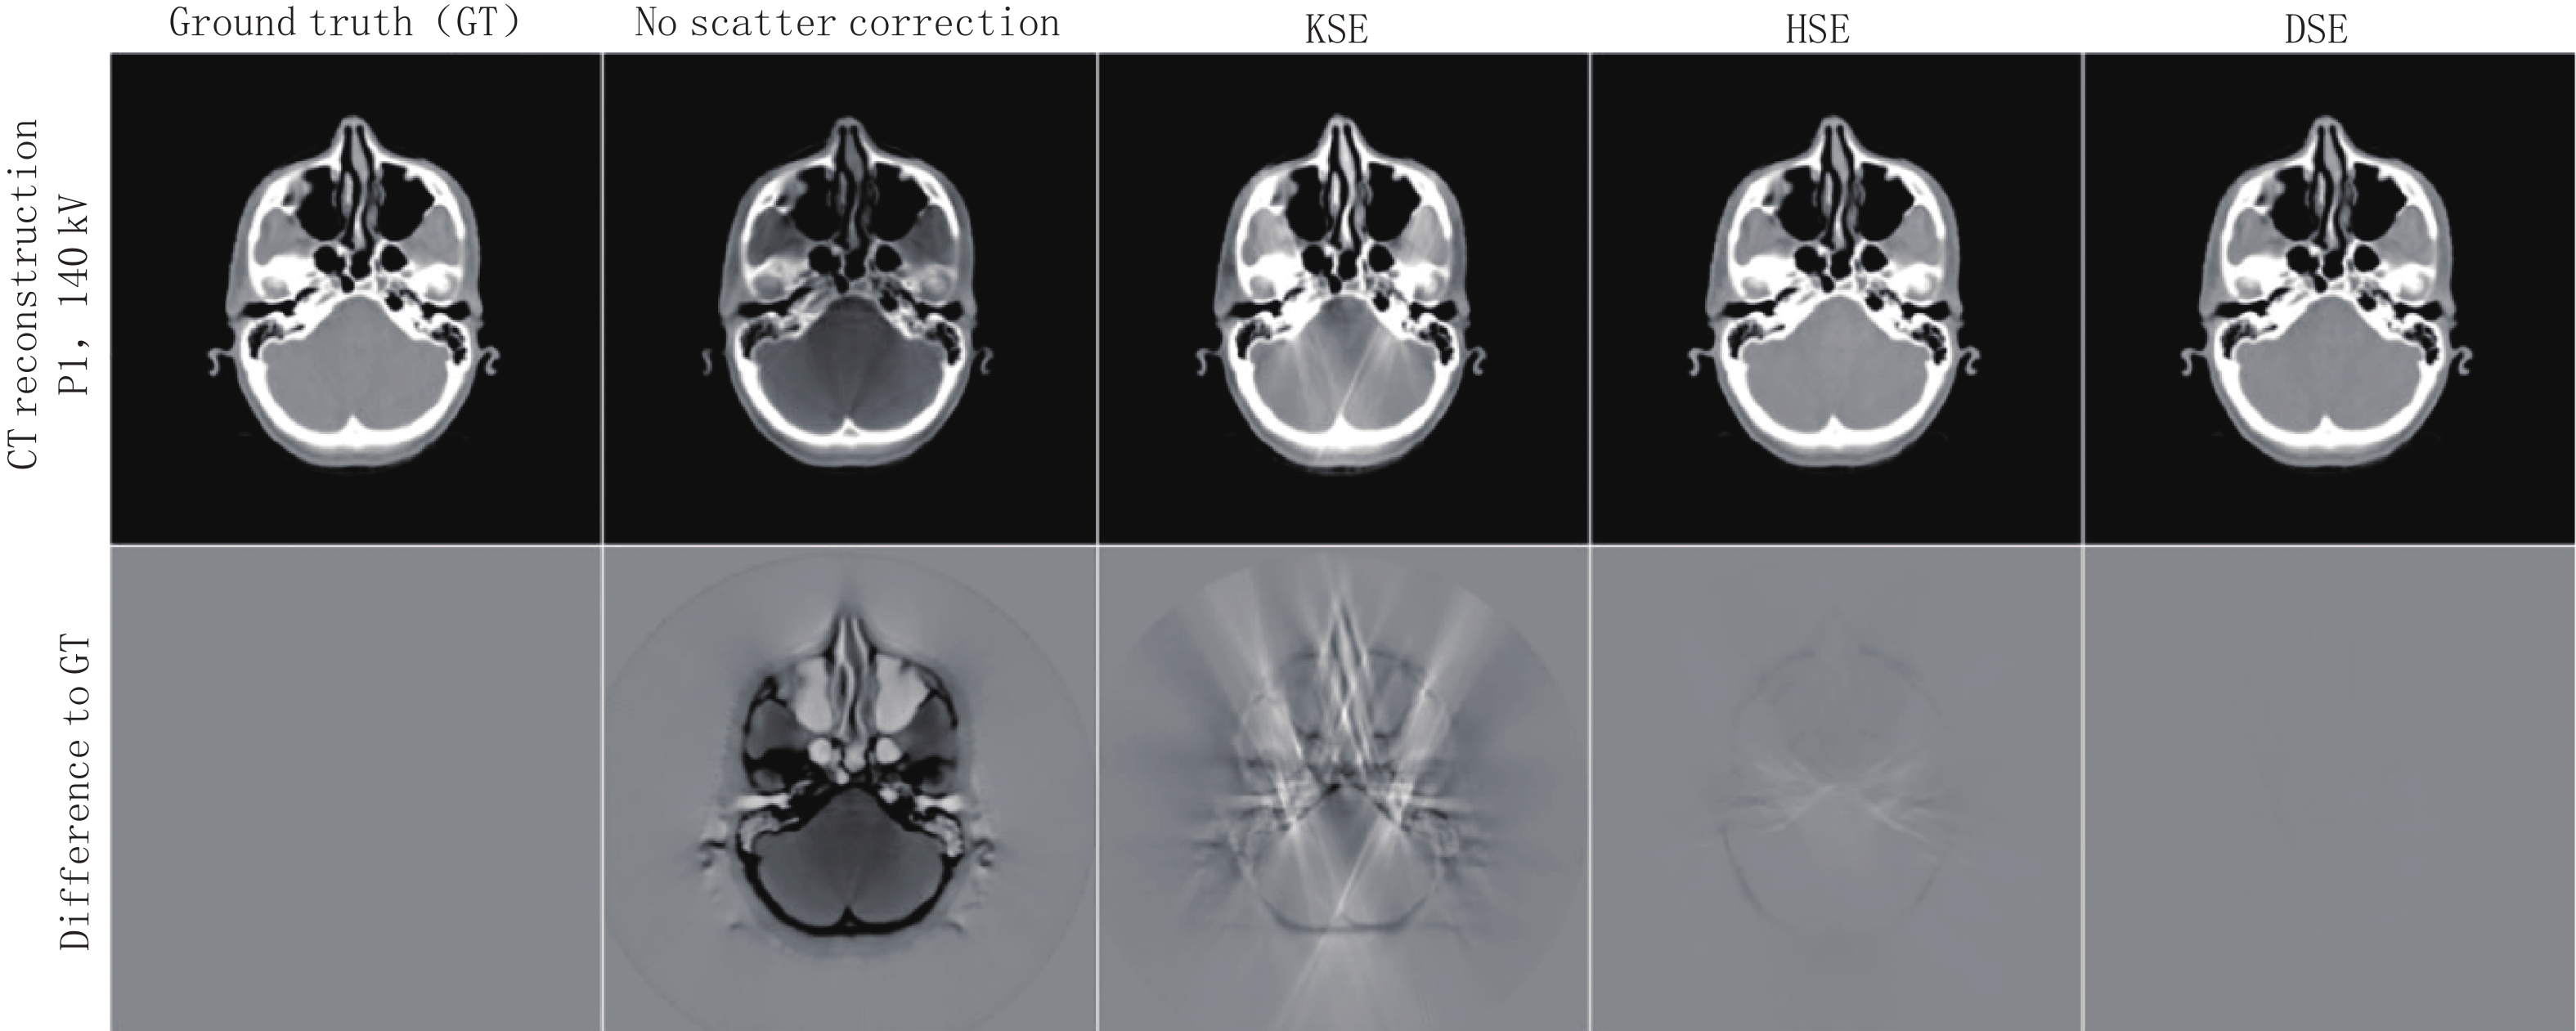

近年来,随着计算机计算能力的提高,深度学习已经发展出许多应用,包括医学图像处理、医学图像分割、医学图像配准、医学图像分类、目标检测等[33]。一些学者也提出使用深度学习方法去除医用CBCT图像伪影,提高图像质量。2018年,Kida等[34]称首次开发出一种用于改善 CBCT图像质量的深度卷积神经网络的方法。此前2017年一篇会议论文[35]中也提出使用深度学习方法进行能谱CT图像的散射校正,该方法校正伪影的流程图如图3所示,首先使用含散射伪影的CBCT图像做深度学习网络模型训练的输入,不含散射伪影的CT图像做网络模型训练的标签来指导网络模型训练的过程,然后使用训练好的模型处理CBCT散射伪影图像,可以很好地解决散射伪影的问题并提高图像质量。

有研究证明深度学习校正结果优于散射核校正和混合校正的传统方法。在CT值准确性方面,深度学习网络方法较传统散射核估计方法和MC混合散射估计方法分别提高了75.5% 和27.7%[5-6],其可视化的校正效果如图4所示。